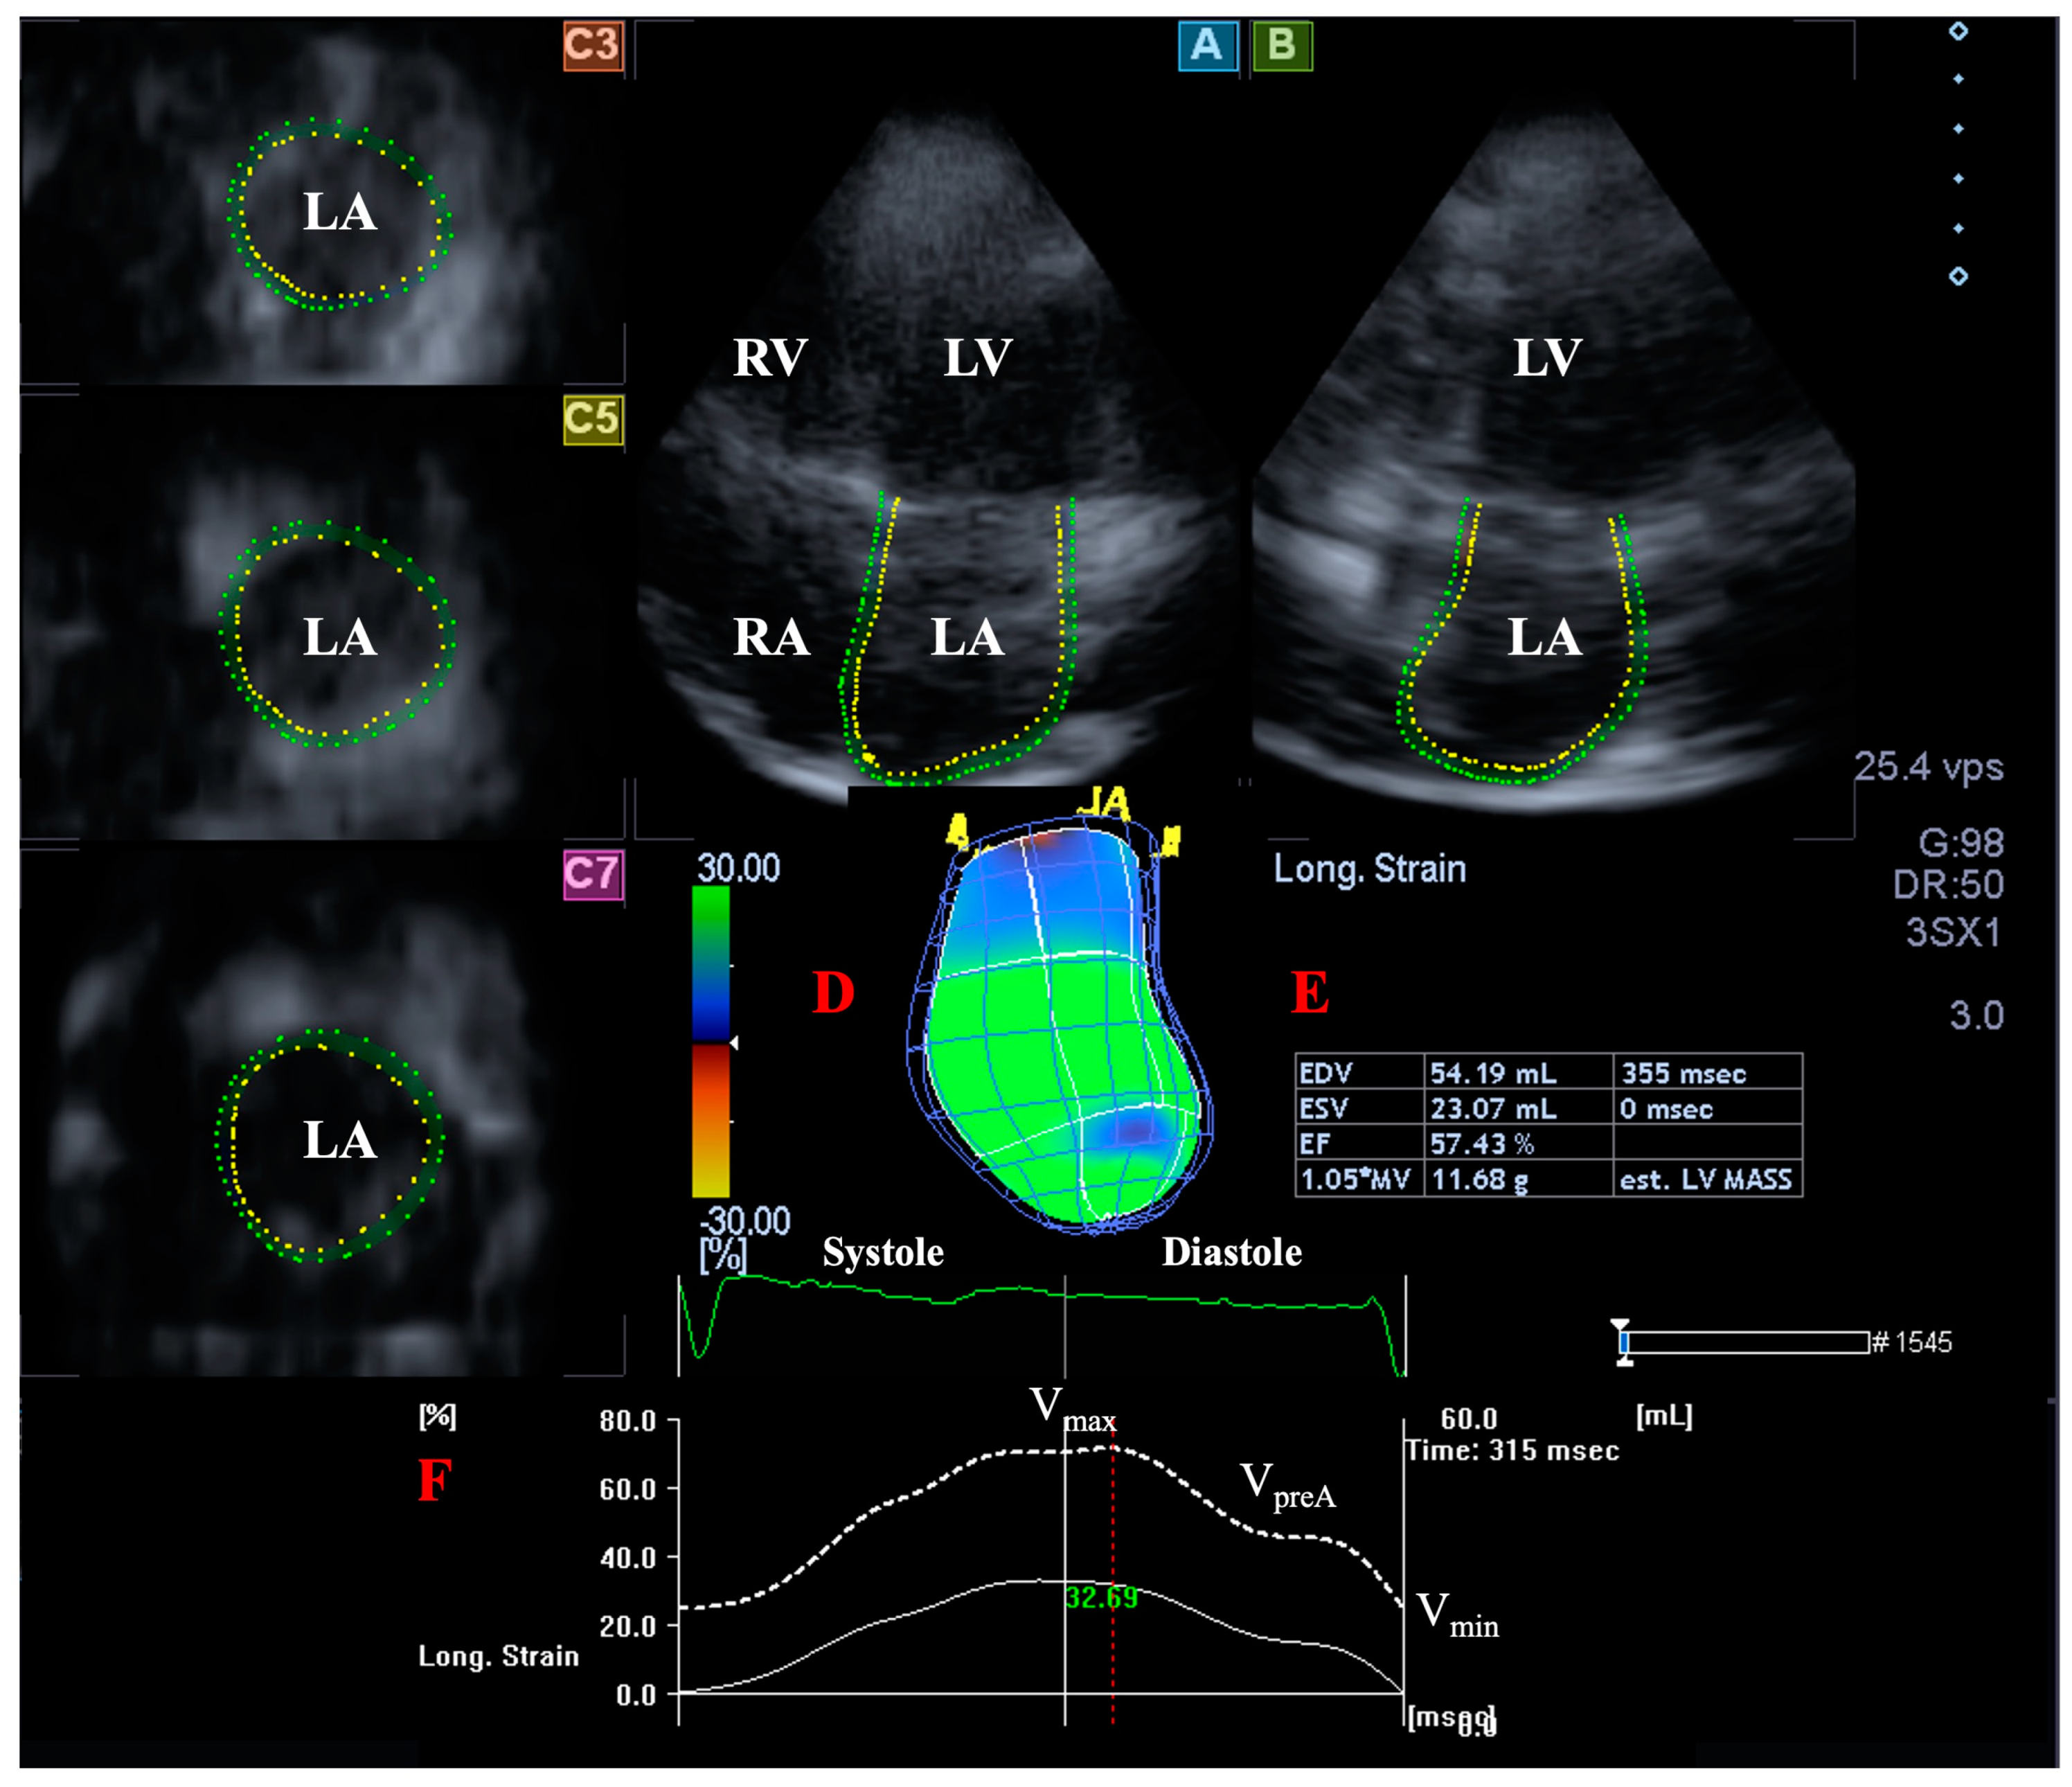

2.5. LA Volume Measurement with 3DSTE

- End-systolic maximum LA volume (Vmax), measured just before mitral valve opening.

- LA volume before atrial contraction in early diastole (VpreA), measured at the time of P wave on ECG.

- Late diastolic minimum LA volume (Vmin), measured just before mitral valve closure.